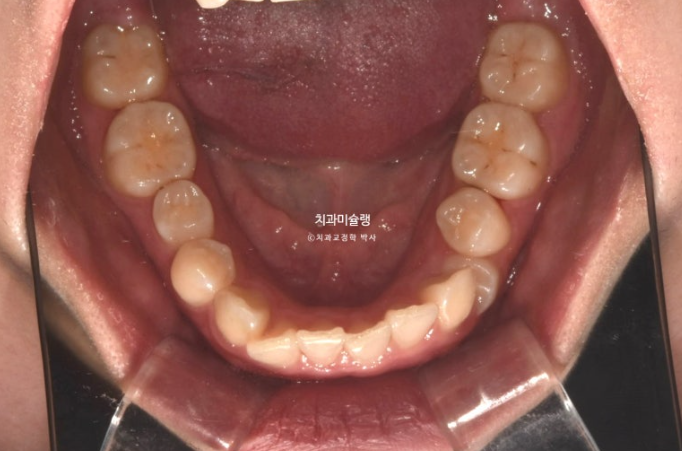

옥니, 덧니, 거미스마일, 중심선 이슈, 약간의 돌출이 함께 있는 상황에서 클리피씨로 거미스마일을 어떻게 해결하는 지 봅시다.

2년 전 교정치료를 위해 온 20대 환자분 입니다.

중심선이 약 2mm 어긋나 있으며 송곳니 덧니가 보입니다.

위 아래 앞니가 깊게 물리는 과개교합도 보입니다.

웃을때 잇몸이 많이 보이는 거미스마일이 있습니다. 특히 위 앞니가 뒤로 쓰러진 옥니 입니다.

작은어금니 하나가 매복되었다시피 깊게 누워있습니다.